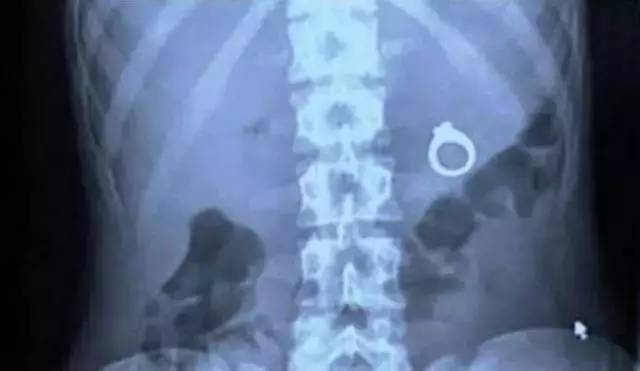

腹部拍片很快确认电池还在胃内,这让专家松了口气,不能让电池在胃内存留时间太长,否则可能还会发生异常不到的意外。消化内科主任娄渊贵立即安排急诊手术,实施全麻下行内镜电池取出术。

无奈之下,医生只能慢慢寻找,15分钟后,终于在油腻的食物残渣下面找到了隐藏的7号碱性电池。